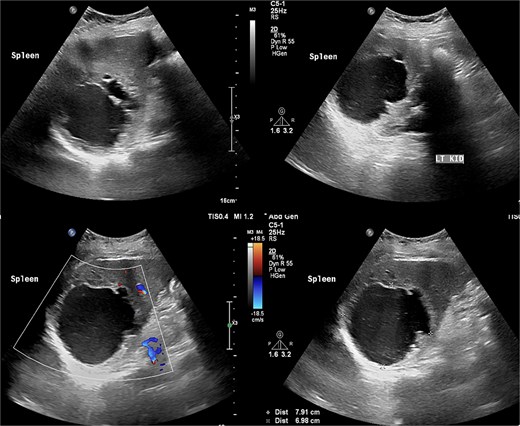

Laboratory results were within normal limits (hemoglobin 120 g/l, WBC 4.72 × 109/l). Abdominal ultrasound showed a well-defined multilocular cystic lesion with internal echoes in the spleen, measuring 7.9 × 6.9 cm, with possible hematoma (Fig. 1). No significant free fluid was detected. A CT scan revealed a large, non-enhancing hypodense splenic cyst with internal septations, calcifications, and multiple peripheral daughter cysts (Fig. 2). The splenic hilum and capsule were intact, with no perisplenic fat stranding. The main differential diagnosis was a type II hydatid cyst. No solid organ injury or significant free fluid was observed.

Abdomen ultrasound revealed well-defined multilocular cystic lesion with internal echoes in the spleen, measuring ~7.9 × 6.9 cm.